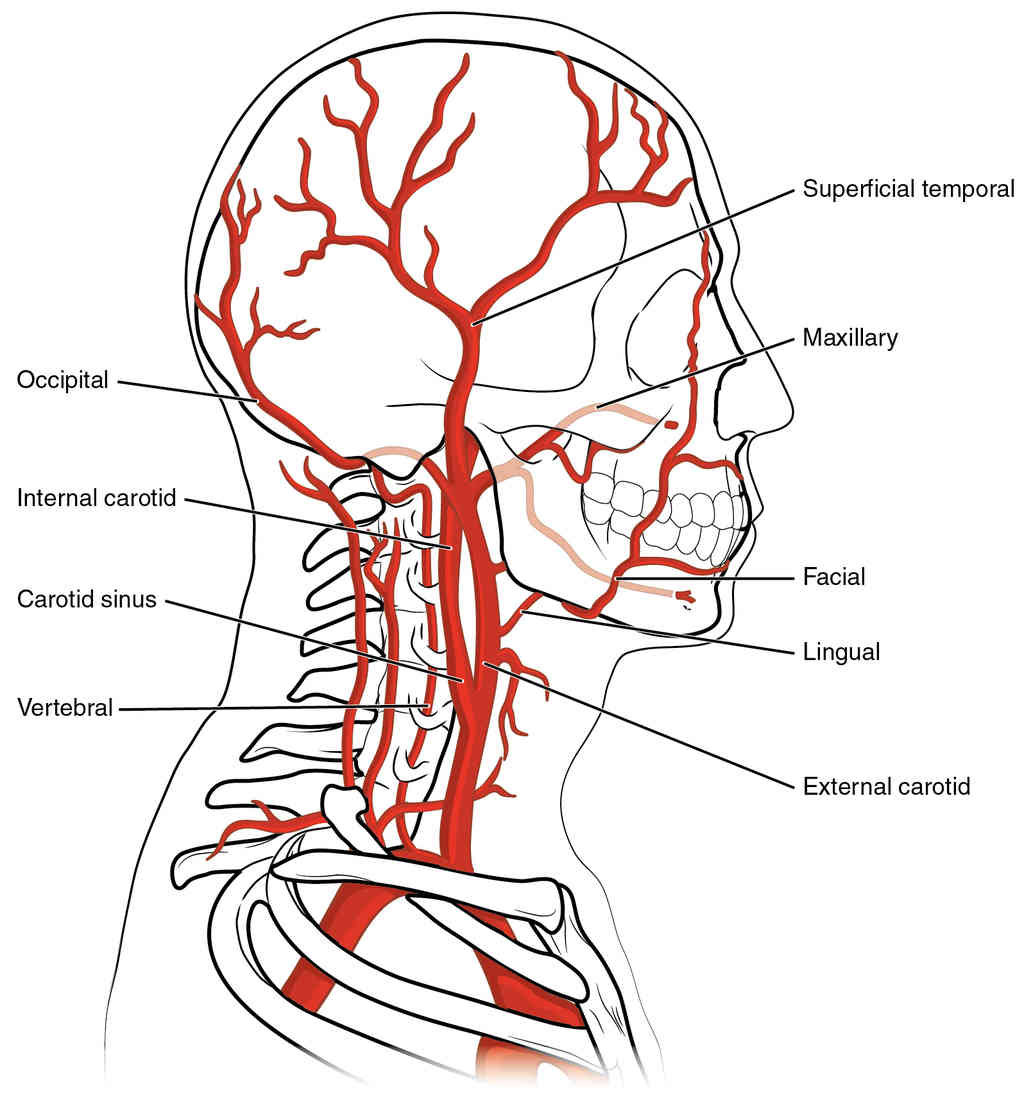

This page is under construction. For now, it is just a resource of the images found in the OpenStax Anatomy and Physiology Handbook. It wil slowly change into a revision tool. Each slide has a number. Use this to refer to the slide. When completed, it will have an unlabelled section, with labelled slides in parallel. On the unlabelled slides, write your answer and use the labelled slide to assess yourself. Keep track by also noting the number on each slide. Improvement at each attempt is important, more so than full marks on a first attempt.